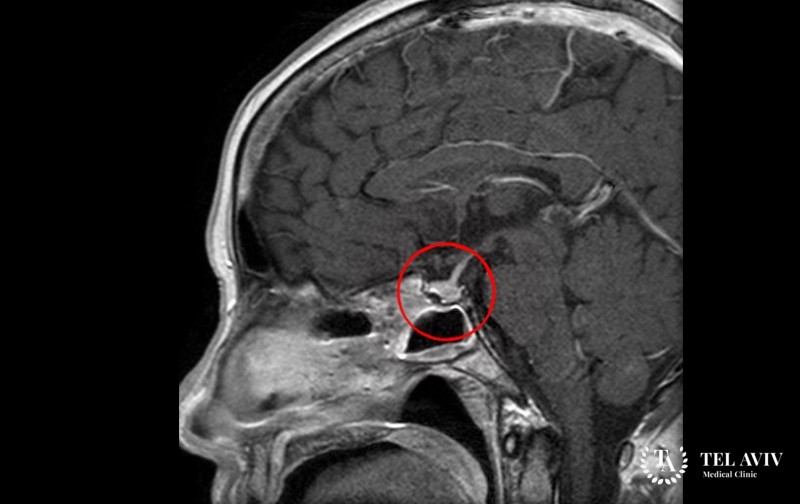

Кортикотропинома относится к доброкачественным образованиям гипофиза, которое развивается из кортикотрофов. Вследствие этого у человека возникает усиленное выделение кортикотропина (АКТГ), которое вызывает возникновение заболевания Иценко-Кушинга, синдрома Нельсона. Данная патология встречается в 10% случаев, в основном у людей 30-50 лет. На ранней стадии заболевание никак себя не проявляет. Поэтому люди зачастую обращаются поздно к врачу.

Вследствие того, что гиперкортицинизм диагностируется еще на этапе микроаденомы гипофиза, наиболее часто врачи используют хирургическое вмешательство для устранения заболевания. К сожалению, адекватной медикаментозной терапии еще не разработано. После проведения операции пациент принимает антисеротониновые, дофаминергические препараты для снижения выработки АКТГ. Также используют симптоматическую терапию для купирования проявлений гиперкортицизма.